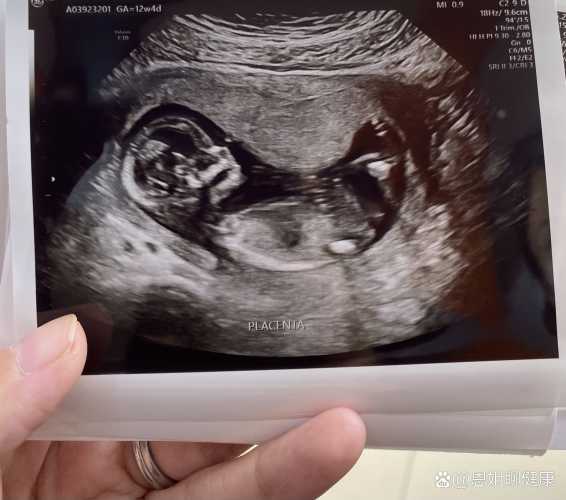

?医学上想准确知道胎儿性别,得等到怀孕中期。像B超检查,大概怀孕20周左右,胎儿体位合适的话,能看清生殖器官。但咱国家法律明确禁止非医学需要的胎儿性别鉴定。

我怀老二的时候,16周就好奇得不行,偷偷问做B超的朋友,结果朋友说太小了看不清。后来24周做四维,医生也没提性别,就盯着宝宝发育情况看。倒是邻居家嫂子,怀孕23周做B超,医生嘟囔了句“这小子腿真长”,后来生了儿子,也算间接“猜”中。但这事儿没个准头,有的宝宝姿势挡着,B超也瞅不清。